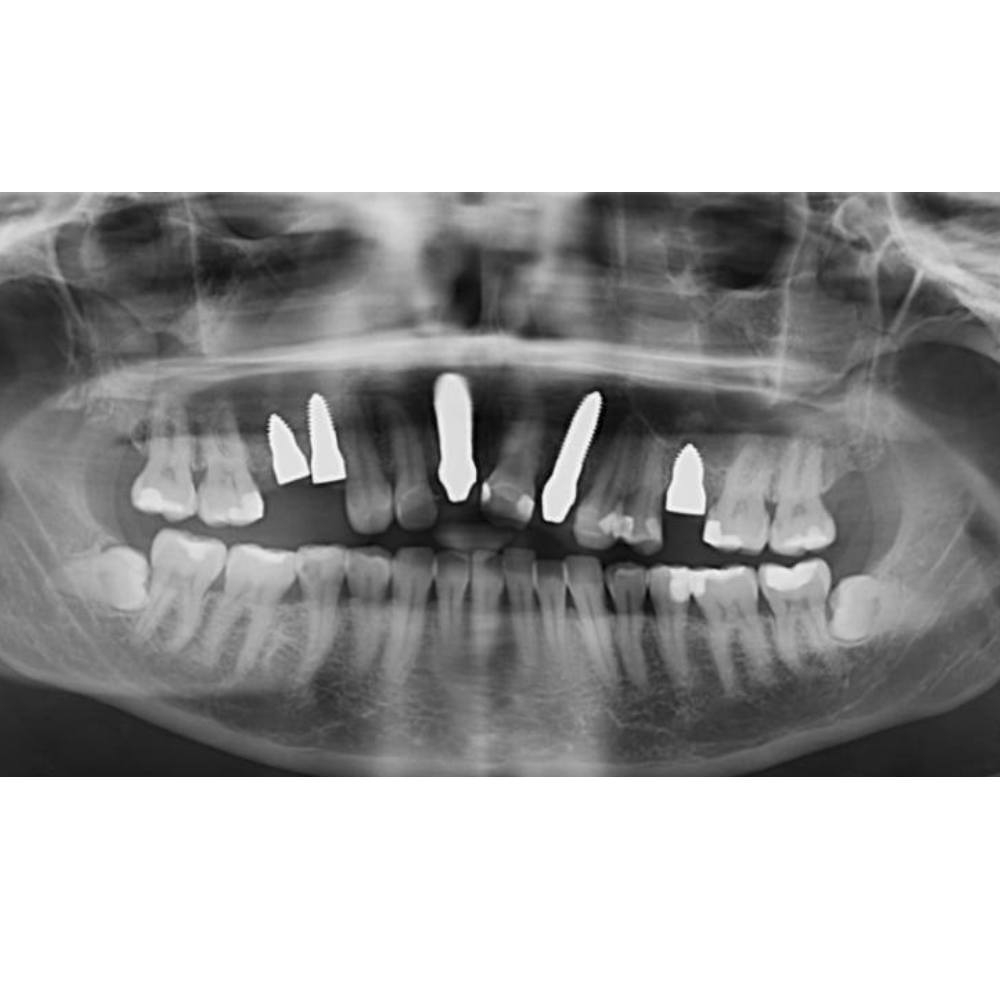

Röntgenbild nach Implantation -

Röntgenologische Dokumentation bei Sofortimplantaten im Seitenzahngebiet